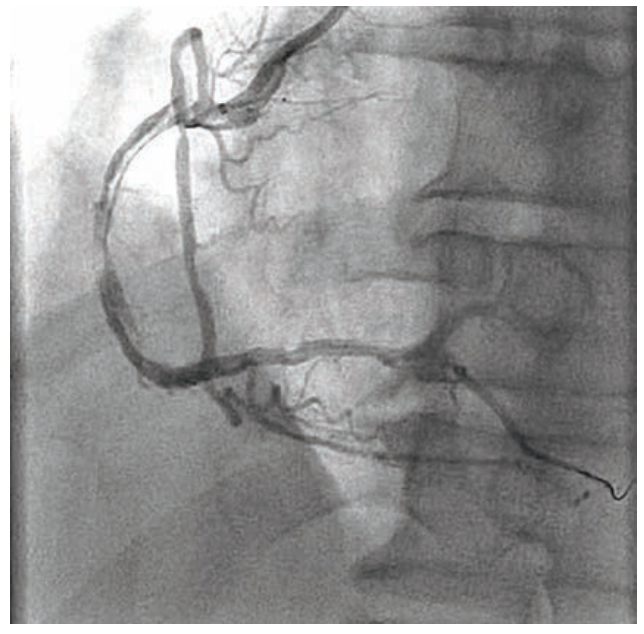

A 57-year-old man was admitted to the hospital for unstable angina. He had undergone an electrocardiogram showing possible old inferior myocardial infarction and echo abnormalities concordant with inferior wall motion abnormalities. A Lexiscan Cardiolite scan showed reversible inferior ischemia. Cardiac catheterization did not show any hemodynamically significant left coronary artery disease. There was a right coronary artery (RCA) chronic total occlusion (CTO) (Figure 1). There were collaterals to the distal RCA via the left anterior descending and circumflex coronary arteries. Left ventriculography showed a left ventricular ejection fraction of 40% to 45% with inferior hypokinesia and inferobasilar hypokinesia. There was no mitral insufficiency.

Owing to the patient’s anginal symptoms and ischemia inferiorly on the Cardiolite imaging, it was elected to open the RCA CTO. An Amplatz Left 1 6 French (Fr) guiding catheter was placed into the anterior takeoff RCA. A Turnpike Spiral microcatheter (Teleflex) with an .014-inch Minamo wire (Asahi Intecc) was initially chosen but could not traverse the stenosis, so the wire was replaced with an .014-inch Sion black wire (Asahi Intecc). This wire appeared to be extraluminal, and was removed and replaced with an .014-inch Mongo wire (Asahi) in the distal vessel, which appeared to track in the true lumen (Figure 2). A 6 Fr GuideLiner (Teleflex) was placed, but in trying to ascertain distal wire position with an injection into the GuideLiner, the vessel appeared to be dissected (Figure 3). We could see the main channel distally, and therefore took a new Minamo 300 wire and placed it into the true lumen. The Mongo wire was removed. However, the Minamo wire would not traverse into the distal vessel, so it was changed for an .014-inch Choice PT Floppy wire (Boston Scientific), which was successful in going distally. We placed a Sasuke dual lumen 145 microcatheter (Asahi Intecc), removed the Choice PT wire, and placed a Balance Middle Weight (BMW) Universal 300 wire (Abbott Vascular). A GuideLiner had been used for support and we attempted to place a Synergy 3.5 mm x 48 mm stent (Boston Scientific). However, the stent would not go forward. It was removed and found to be intact on inspection. The stent was replaced with a 3.0 mm x 30 mm Monorail Emerge balloon (Boston Scientific) for further dilatation of the RCA to 6 atmospheres (atm) for overlapping 15-second inflations. A third inflation of 12 atm for 35 seconds was performed and the balloon was removed. A 3.0 mm x 38 mm Synergy drug-eluting stent (Boston Scientific) was not able to be placed adequately distally, and was removed, inspected, and found to be intact. It appeared that the GuideLiner might be preventing some forward motion of the stent and it too was removed. There was, on angiography, a flow abnormality consistent with a small branch wire perfusion abnormality. There was no clear-cut staining. An echo showed no evidence of pericardial fluid and no tamponade physiology. It was felt that this should be addressed and so a 1.5 mm x 12 mm Takeru balloon (Terumo) was inflated to 6 atm for 20 seconds, though this did not resolve the flow abnormality. Ultimately, a 2.5 mm x 15 mm PK Papyrus covered stent (Biotronik) was delivered to the site of flow abnormality and deployed to 6 atm for 60 seconds. Angiography after balloon deflation showed no further flow into the branch (Figure 4).